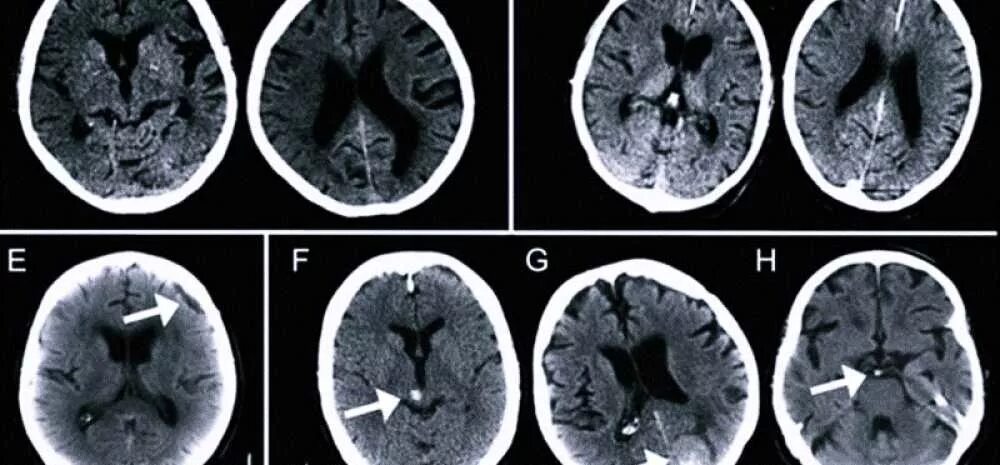

Данные мрт